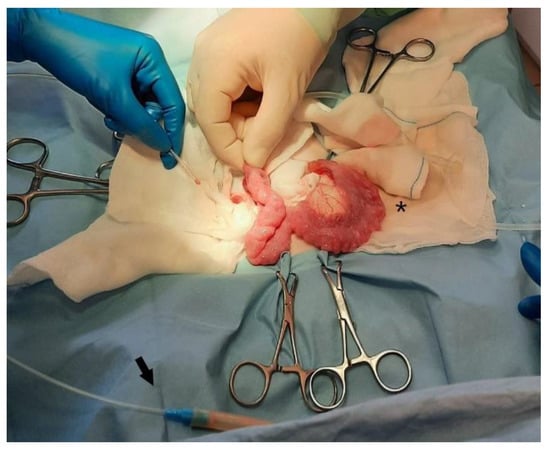

3. Treatment and Follow up